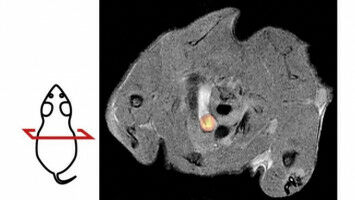

Gesundheit - Biowissenschaften - 16.03.2023

Forschende der Universität Tübingen haben ein neues Verfahren entwickelt, mit dem sich Atherosklerose im Mausmodell besser erforschen lässt. Die nicht-invasive Bildgebungsmethode soll neue Wege eröffnen, Gefäßverengungen als Ursache von Herzinfarkten und Schlaganfällen besser zu verstehen und zu behandeln.